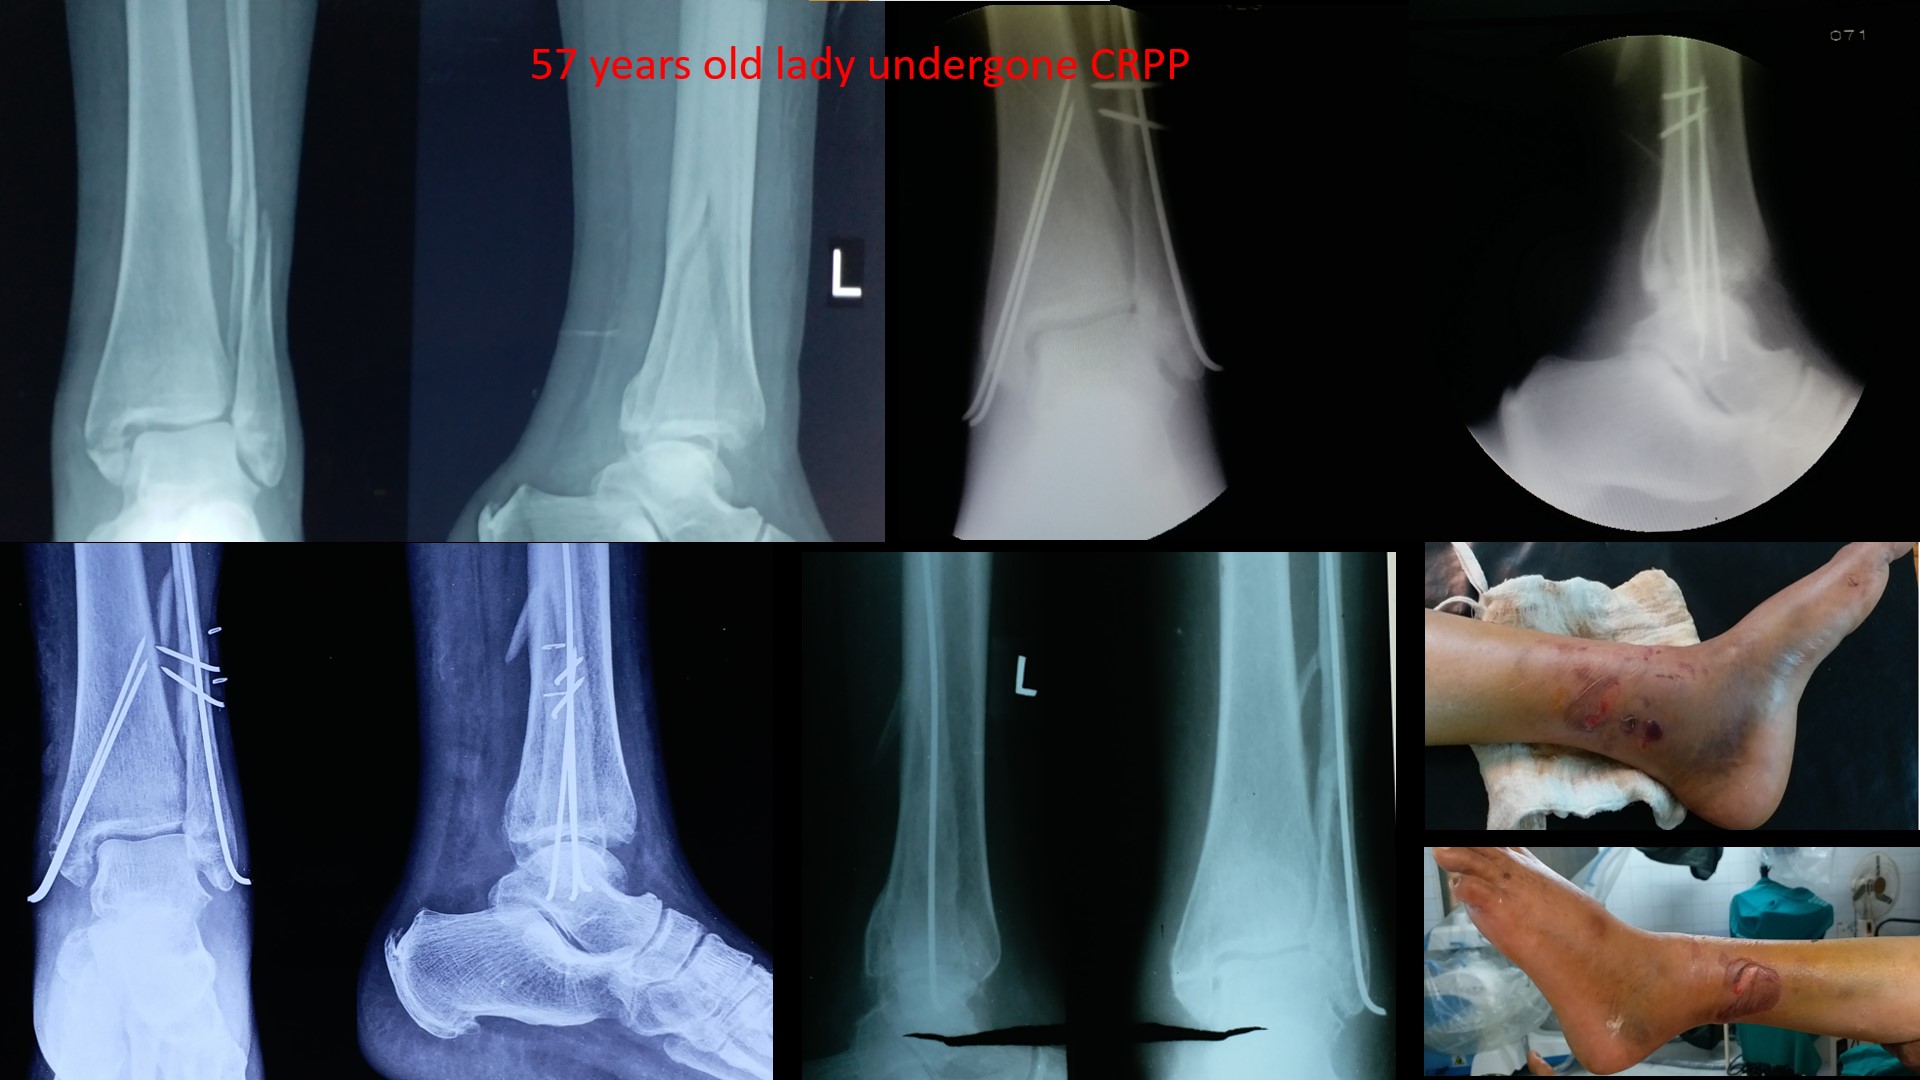

ANKLE